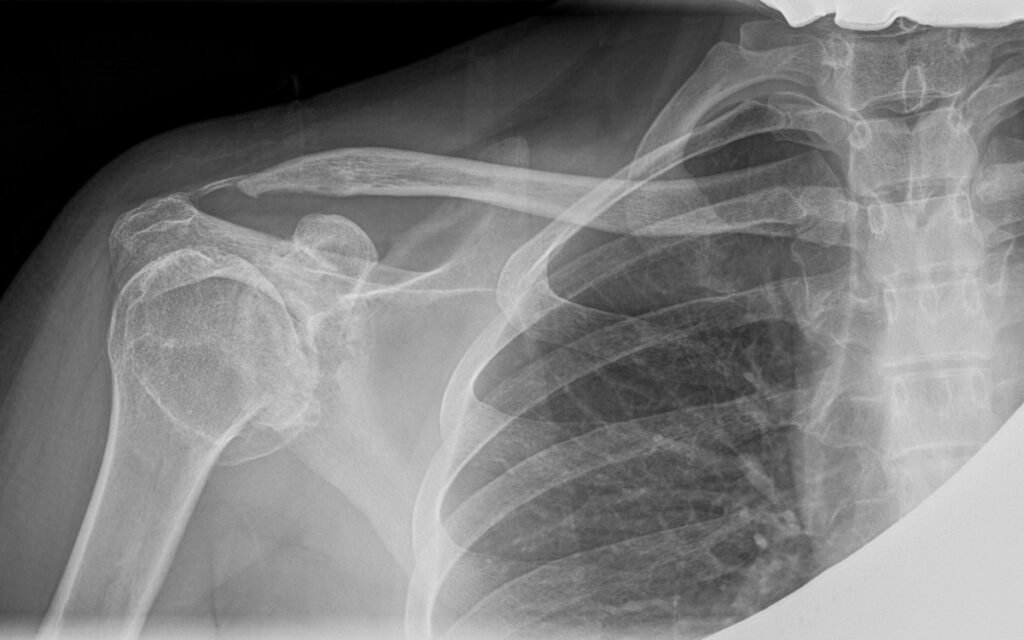

Diagnosis and imaging

Imaging plays a key role in confirming the diagnosis and guiding treatment decisions. Common investigations include:

These tools help Dr Hockings understand the severity of arthritis, involvement of the rotator cuff, and suitability for surgical or non-surgical care.